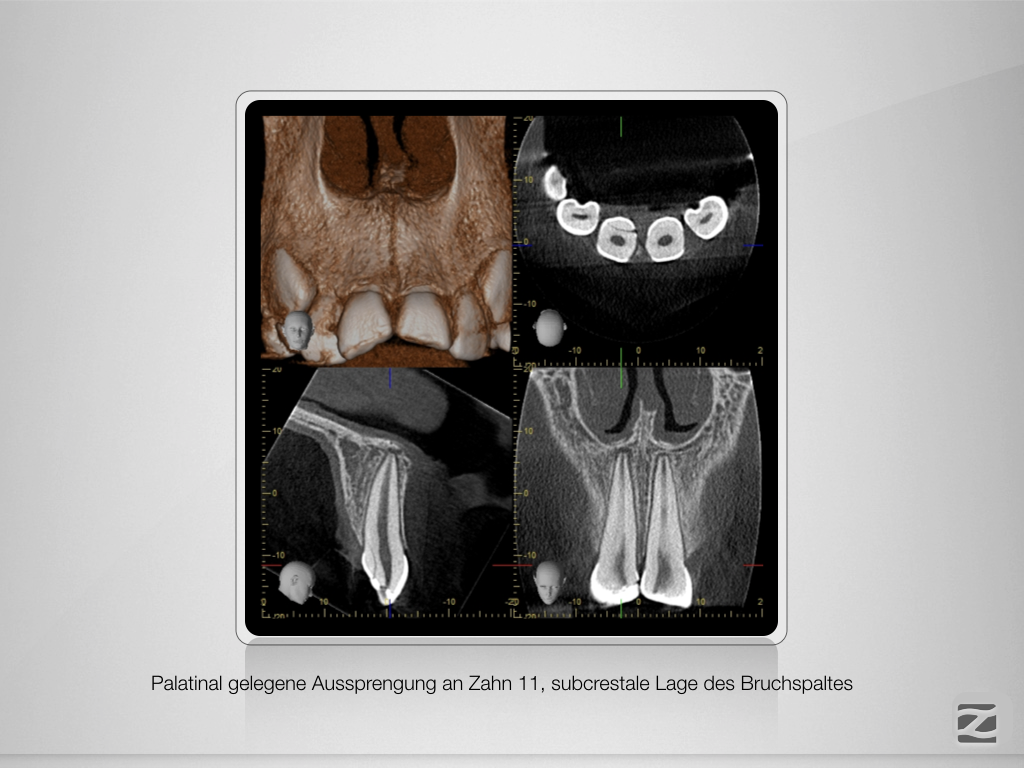

And the show goes on-Trauma, die Zweite.